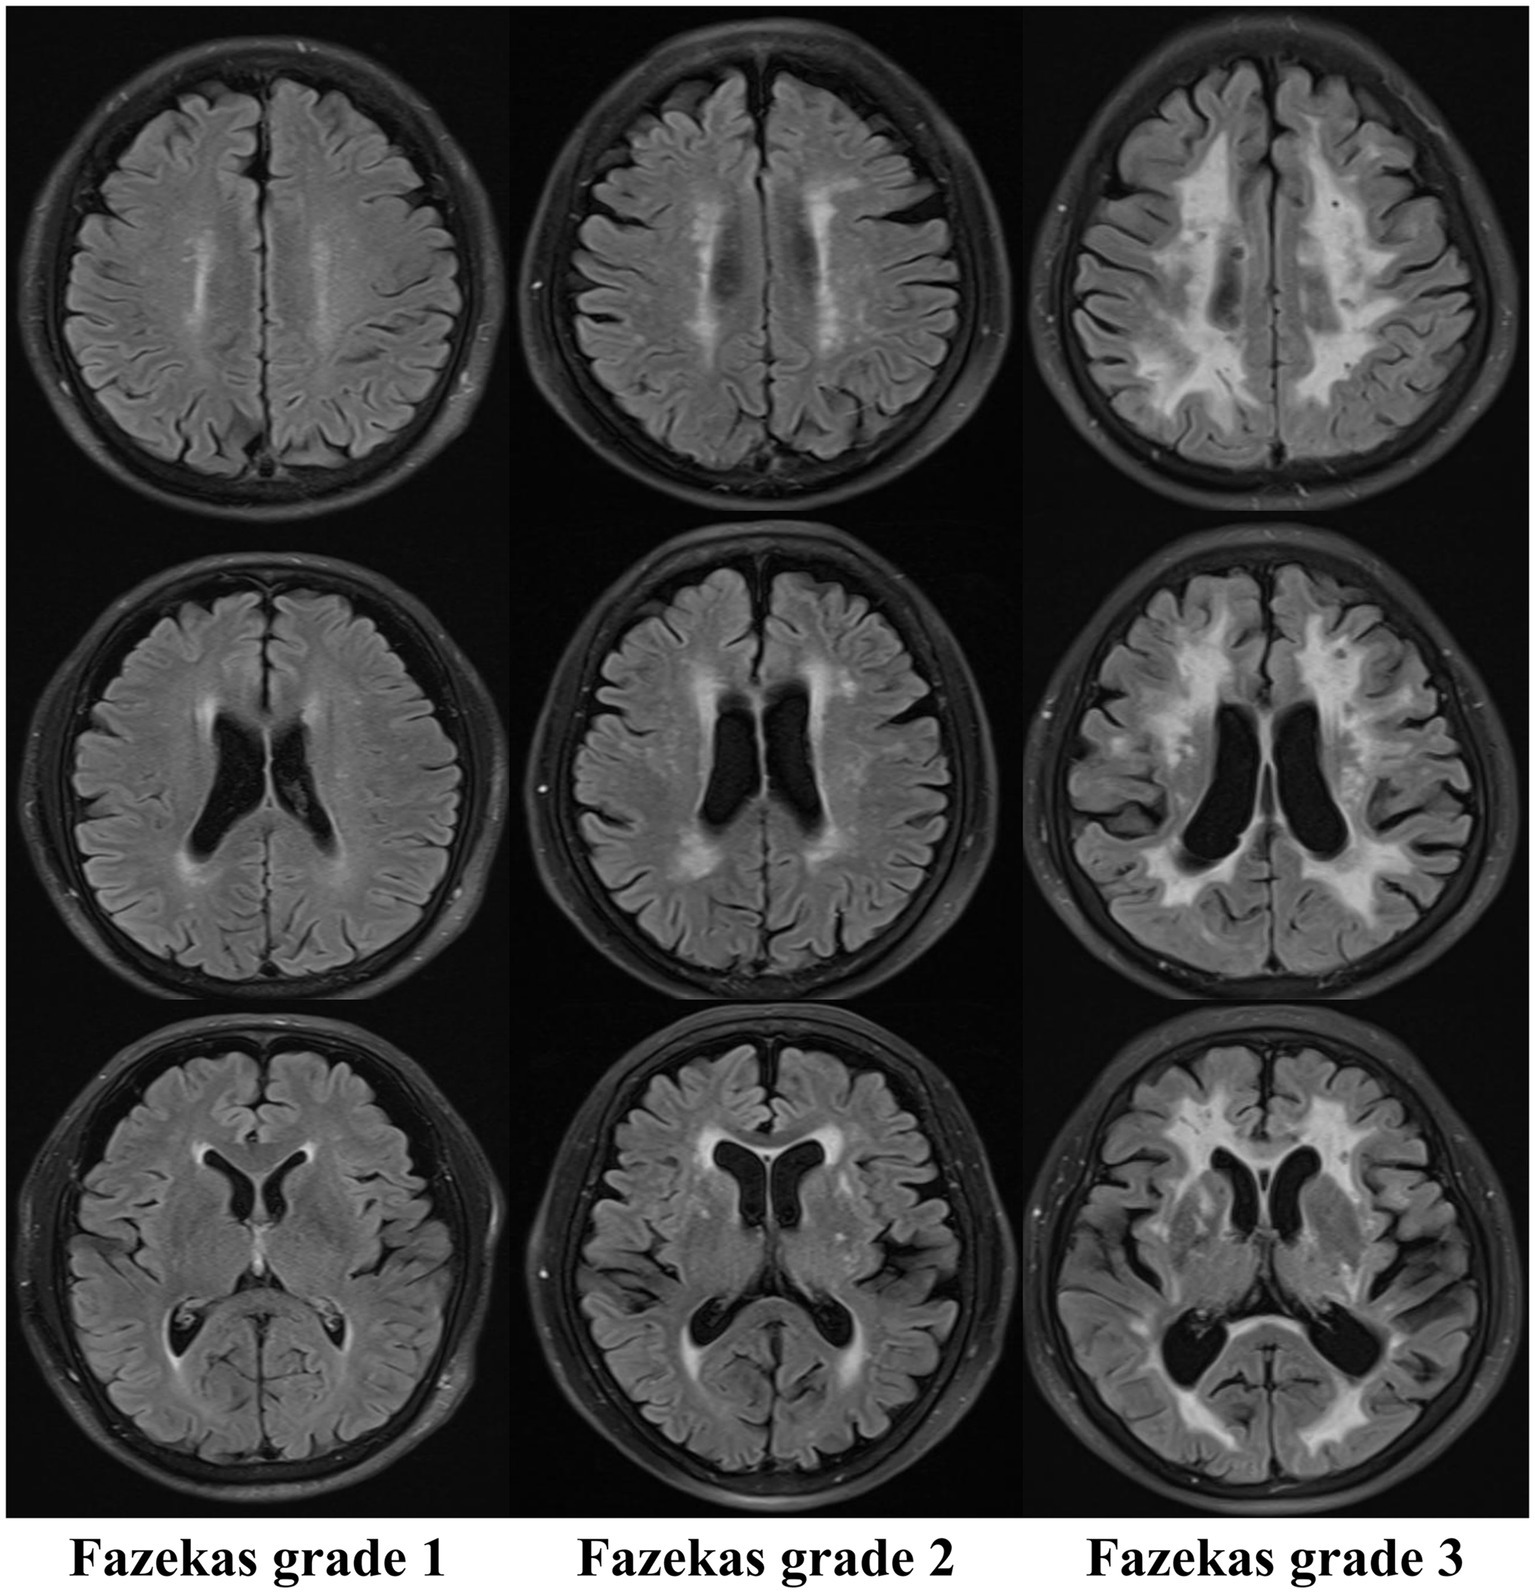

The Fazekas grading system is the classical imaging standard for assessing the severity of WMH (9–11, 43). The most common classification of WMHs is location, as periventricular white matter hyperintensities (PWMHs) around the lateral ventricles and deep white matter hyperintensities (DWMHs) in the deep part of the subcortical white matter are assigned grades 0–3. According to the morphology of the lesions, PWMHs are divided into no lesions (0 grade), cap or pencil-thin lesions (1 grade), smooth halo lesions (2 grade) and irregular extension into the deep white matter (3 grade). DWMH scores are assigned as follows: no lesion (0 grade), punctate lesions (1 grade), lesions beginning to fuse into plaque (2 grade) and large areas of lesions fused into patches (3 grade). The modified Fazekas classification was as follows: grade 1 (scattered punctate lesions with a speckle-like appearance), grade 2 (some lesions fused to a plaque), and grade 3 (large lesions fused to a patch). The characteristic MR imaging findings on white matter hyperintensity lesions refer to Figure 2 for details.

Figure 2

Characteristic MR imaging findings on white matter hyperintensity lesions (Fazekas).